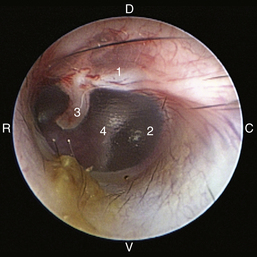

image

Figure 20-8 Normal canine tympanic membrane of the left ear. 1, Pars flaccida; 2, pars tensa; 3, stria mallearis; 4, bulla septum; C, caudal; D, dorsal; R, rostral; V, ventral.

(Courtesy of Dr. Lynette Cole, The Ohio State University, Columbus, Ohio.)